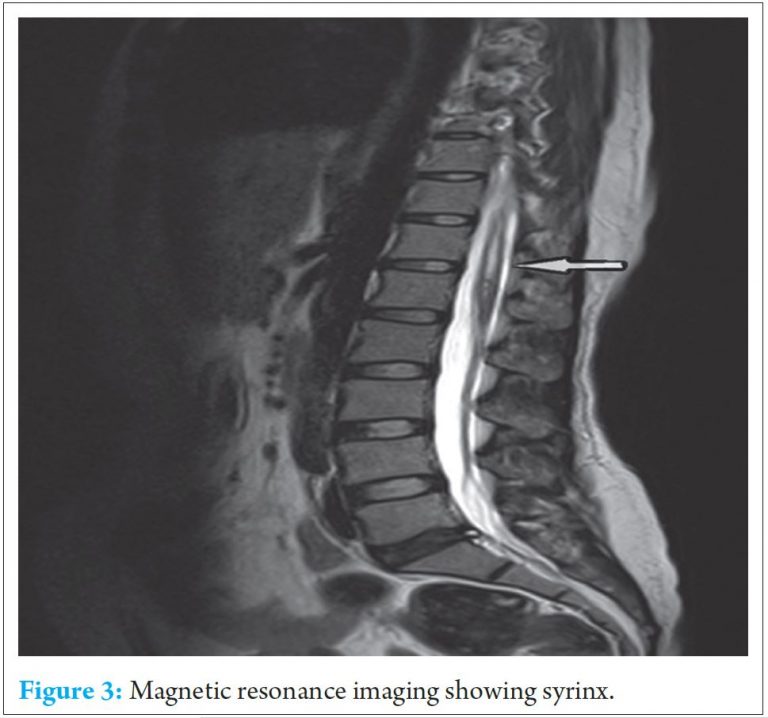

MRI of whole spine was done which show syrinx at D7, D9, D10 & D12 and L1 level. (Refer Fig.3)